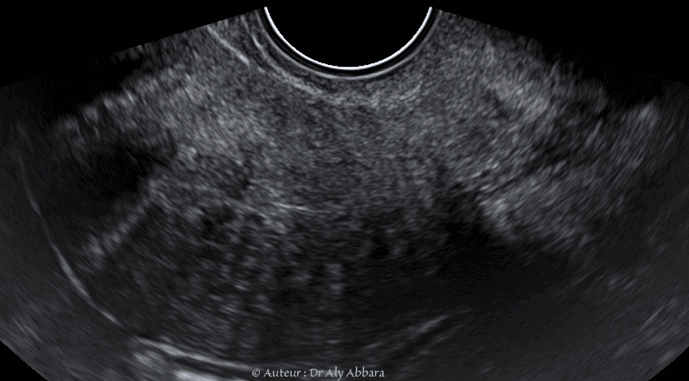

Images échographiques et cliniques animée montrant un myome endocervical polypoïde accouché par l'orifice externe du col utérin de 30 x 24 x 13 mm de diamètre.

Il s'agit d'images pré-opératoires ; per-opératoires (après la myomectomie) puis un mois après l'ablation chirurgicale de ce myome.

Ce fibrome est à l'origine de métrorragies post-coïtales (traumatiques).